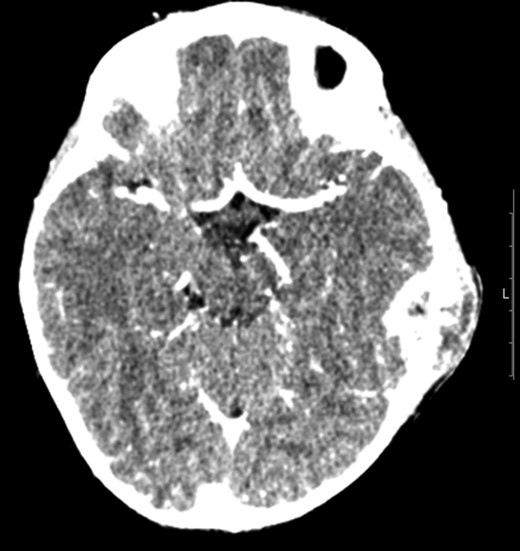

A CT scan of the patient at this point showed mastoiditis, a subperiosteal abscess and extradural abscess with extensive bony defects (Figs 1 and 2). The patient was initially started on IV ceftriaxone and metronidazole. Upon discussion with ENT specialists he underwent a left sided mastoid exploration and drainage of the extradural and peri sigmoid sinus collection on Day 2 of his admission. Surgical exploration found a large parietal subperiosteal abscess with bony defects and granulation tissue connecting with an extradural abscess. Histological diagnosis showed evidence of granulomatous osteomyelitis due to necrotizing granulomatous inflammation. Initial Zeihl-Neelson and Wade Fire stains for acid fast bacilli in tissue culture were negative.

Transverse computed tomography (bone window) image showing a left sided mastoiditis (white asterisk) bone extensive cortical bony destruction involving left petrous, squamous and mastoid bone as well as the adjacent parietal bone.